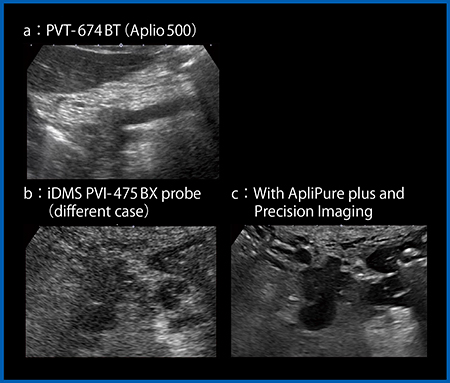

図3は,膵臓がんにおけるPVT-674BT(Aplio 500)とiDMS PVI-475BX(別の症例)の比較である。PVT-674BTでは画像は全体に不明瞭であり,深部は減衰している(図3 a)。一方,iDMS PVI-475BXはSNRが高いため画像に多少のざらつき感があるが,腫瘍がはっきりととらえられている(図3 b)。さらに,ノイズやアーチファクトの低減技術“ApliPure plus”と,境界や構造物の視認性を向上させる技術“Precision Imaging”を適用することで,分枝膵管の拡張や腫瘍の輪郭もはっきりと観察できる(図3 c)。深部臓器である膵臓の1.5cmの腫瘍でもここまで描出できており,iDMS PVI-475BXが,いかにペネトレーションと分解能を両立させているかが理解できる。

図3 膵臓がんにおけるPVT-674BT(a)とiDMS PVI-475BX(b,c)の比較